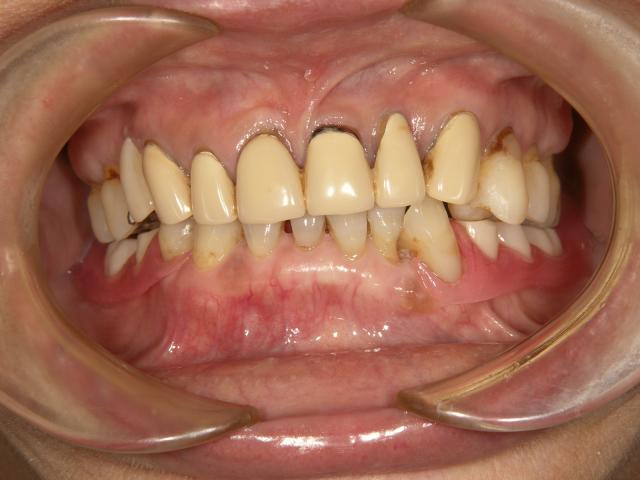

テレスコープタイプの入れ歯(上顎)

2007/04/27

70代女性 担当:院長

義歯が磨り減ってよく噛めない。

唇を噛んでしまう。

前歯の部分が見えないので、自然に見えるようにして欲しい。

術前space術後

術前 術後

1年ほどかけて咬合を挙げてから新義歯作成しました。